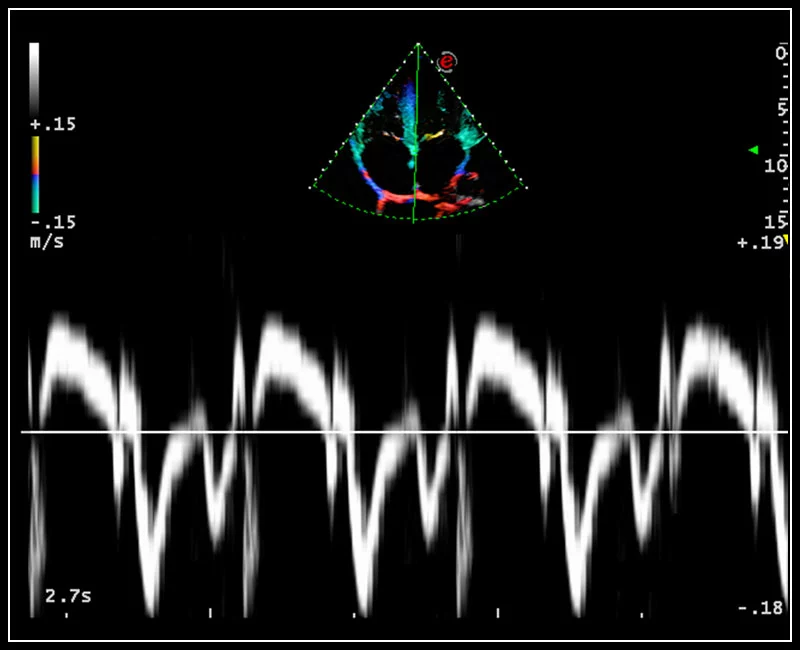

MyLab™9 Platform - Tissue Velocity imaging to quantify septal velocity and dyssynchrony

MyLab™9 Platform - Tissue Velocity imaging to quantify septal velocity and dyssynchrony